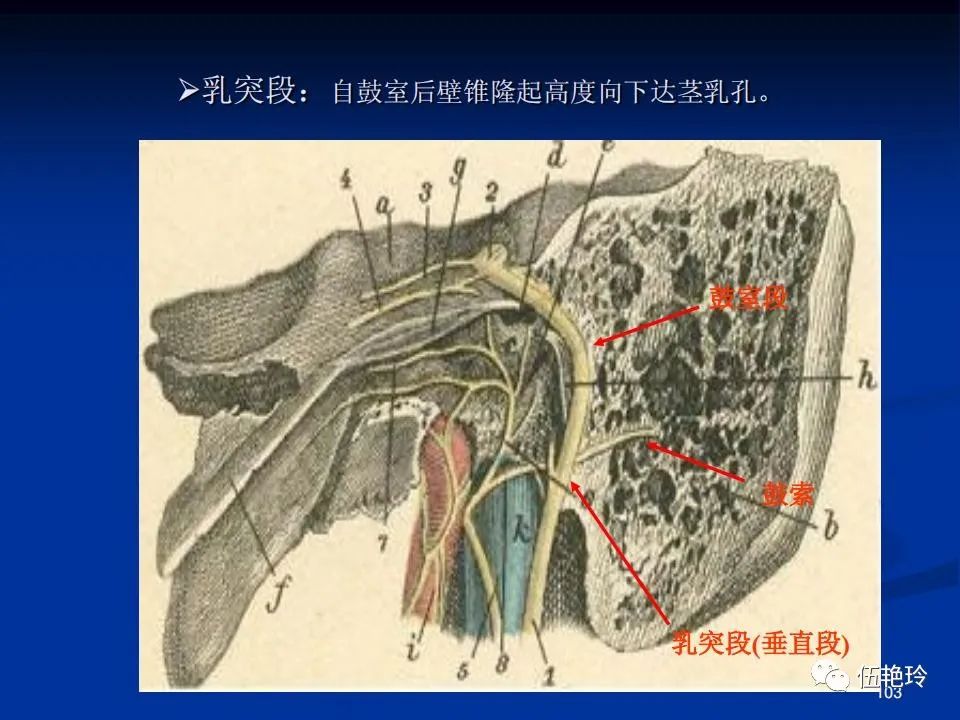

耳与面神经的解剖